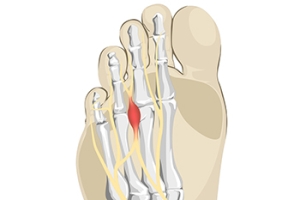

When to Have Foot Surgery

Making the decision about whether to undergo foot surgery is a difficult and highly personalized process. In consultation with a podiatrist and surgeon, you can receive the information you need to make an informed decision. Generally speaking, if you notice that a foot affliction you have is causing your skin to react negatively or your foot to become deformed, foot surgery might be a good option for you. Additionally, if you notice that your affliction is not responding to any medication your podiatrist has prescribed or any orthotics you might be wearing, then foot surgery might be a suitable last resort. There are a variety of conditions that may ultimately merit surgery. For example, particularly bad cases of Morton’s neuroma might require foot surgery. Specifically, the nerve that is affected between the toes because of Morton’s neuroma, may be successfully removed by foot surgery. Of course, foot surgery can also create detrimental consequences in some cases. There may be complications as a result of the surgery or your joint movement may be restricted. Alternatives to surgery might include performing specific exercises or adjusting footwear. You can make this difficult decision about undergoing surgery with the guidance and advice of your podiatrist.

Common Symptoms of Morton’s Neuroma

Research has indicated that the foot condition known as Morton’s neuroma is generally simple to diagnose. The common symptoms that many people experience with this ailment can include a tingling sensation between the second and third toes, or the fourth and fifth toes. It may begin after wearing specific types of shoes, or from walking or standing for an extended period of time. Many people can develop this condition from wearing high heels. This can be a result of a lack of adequate space for the toes to move freely in. A clicking feeling and sound may be felt in the ball of the foot, and it can feel uncomfortable. Many people often equate this feeling with the sensation of stepping on a marble, or having an out of place seam from a sock. Additionally, the toes can separate with a large Morton’s neuroma, and medical attention is needed. The toes may become numb, and it can be quite painful to walk. If you have any of these symptoms, it is advised that you place yourself under the care of a podiatrist who can use various conservative methods, or possibly even perform surgery, to treat Morton’s neuroma.

Morton’s Neuroma

Morton's neuroma is a painful foot condition that commonly affects the areas between the second and third or third and fourth toe, although other areas of the foot are also susceptible. Morton’s neuroma is caused by an inflamed nerve in the foot that is being squeezed and aggravated by surrounding bones.

Morton’s neuroma is a very treatable condition. Orthotics and shoe inserts can often be used to alleviate the pain on the forefront of the feet. In more severe cases, corticosteroids can also be prescribed. In order to figure out the best treatment for your neuroma, it’s recommended to seek the care of a podiatrist who can diagnose your condition and provide different treatment options.